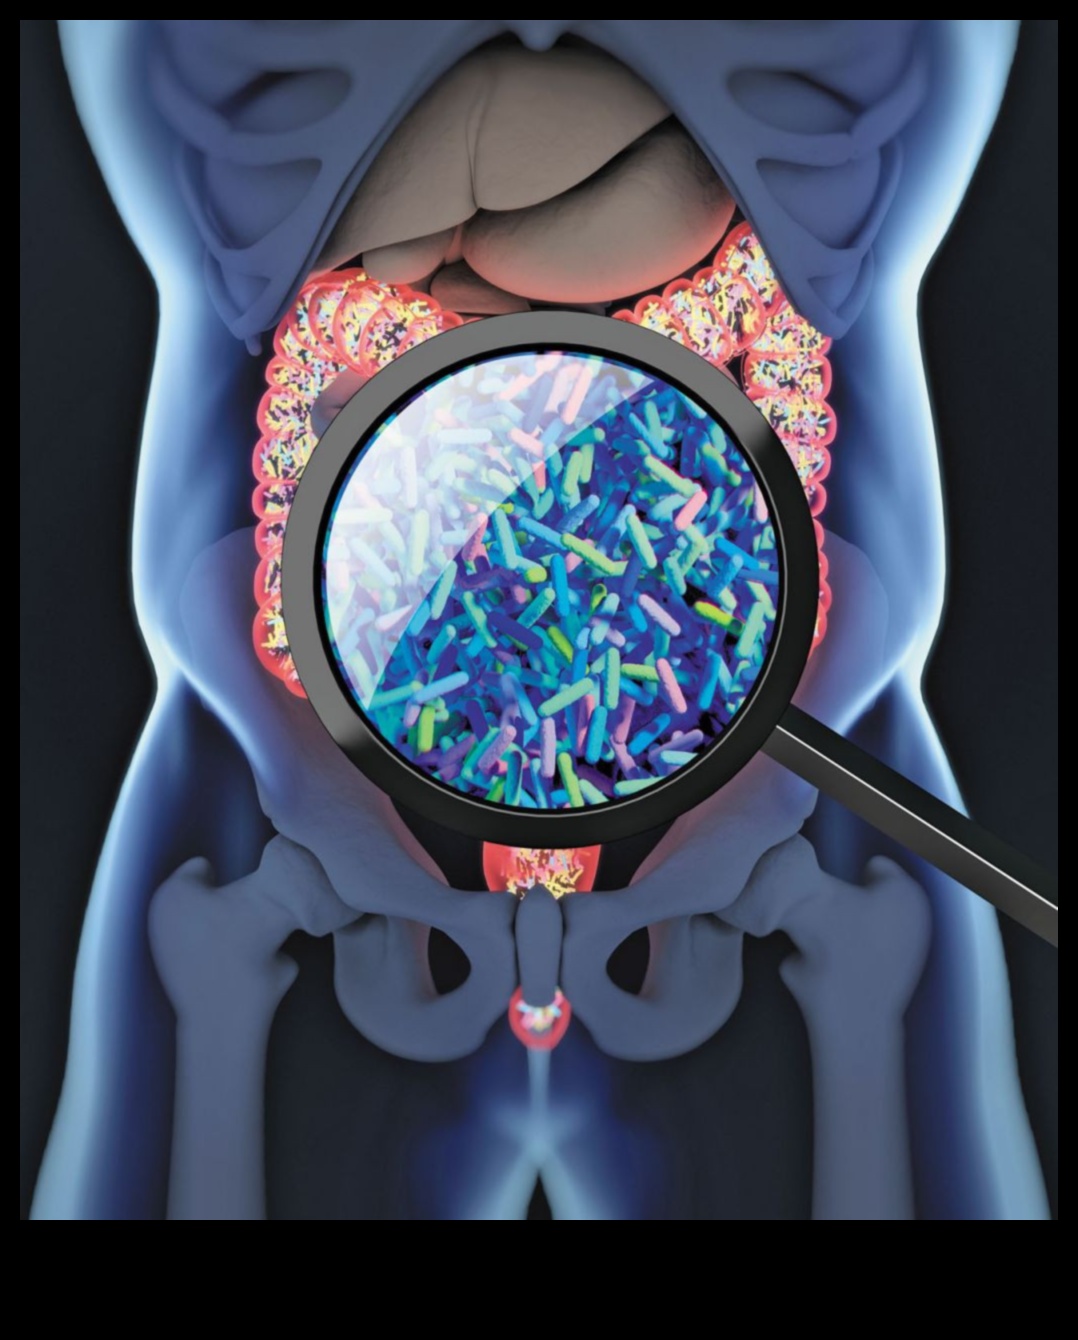

Zarnu mikrobiota ir triljoniem baktēriju, vīrusu un citu mikroorganismu apkārtne, kas uzturas cilvēka gremošanas traktā. Tiem mikrobiem ir svarīga uzdevums gremošanu, imunitāti un vielmaiņu, un cilvēki arvien pietiekami daudz notiek saistīti izmantojot svara zudumu un aptaukošanos.

Zarnu mikrobioms ir triljoniem baktēriju, vīrusu un citu mikroorganismu apkārtne, kas uzturas cilvēka gremošanas traktā. Tiem mikrobiem ir svarīga uzdevums gremošanu, imunitāti un vielmaiņu, un cilvēki arvien pietiekami daudz notiek saistīti izmantojot aptaukošanos un svara zudumu.